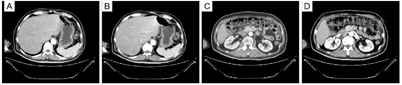

患者,男性,54岁,入院前10天无诱因出现腹胀,呈进行性加重,无法自行缓解。入院前2天行胸腹增强CT示:两肺多发实性结节,纵膈及食管下段多发肿大淋巴结,腹膜、网膜、肠系膜弥漫性增厚并多发软组织低密度影,腹盆腔积液(图1)。胃镜检查未见肿瘤病灶。入我科前1小时,出现胸闷、气促。2017年8月于外院行腰背部黑痣切除术,当时病理结果回报"皮内痣",家族中无类似病史。

予3周期上述方案治疗后,患者腹胀、胸闷症状明显缓解,全腹增强CT示:腹水明显减少,腹膜、网膜、肠系膜及膀胱直肠陷凹弥漫腹膜增厚伴多发结节,较前明显减少。

行3周期上述治疗后,患者腹胀、胸闷症状明显缓解,全腹增强CT(图8):腰背部原术区未见肿瘤复发征象;腹膜、网膜、肠系膜及膀胱直肠陷凹弥漫性增厚伴多发结节,但较前明显减少,提示目前治疗方案有效。